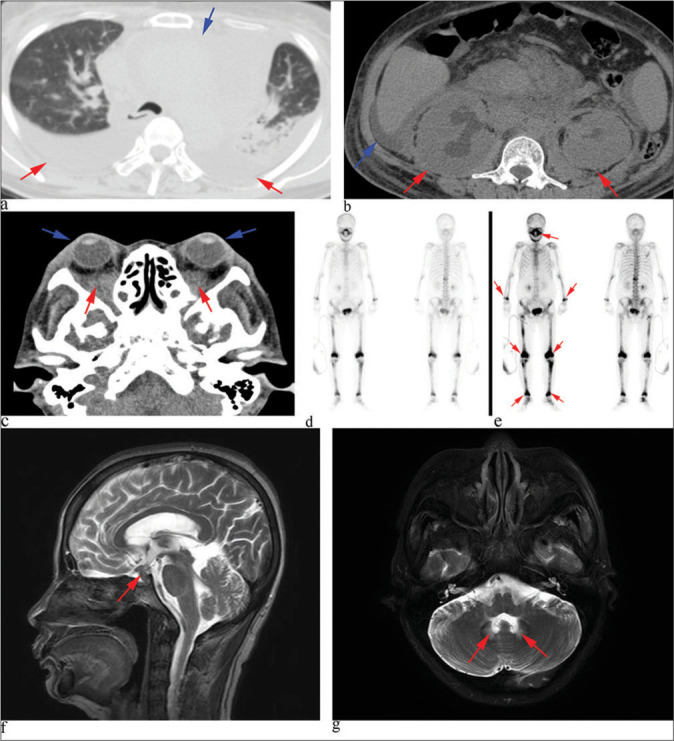

Langerhans cell histiocytosis (LCH) and Erdheim-Chester disease (ECD) are exceptionally rare disorders characterized by varied clinical presentations, posing several challenges for clinicians. The concomitant occurrence of LCH and ECD is exceedingly rare and has no known etiology. In this report, we present a rare case of mixed histiocytosis (both ECD and LCH) with multisystem involvement. The patient, a 49-year-old female, initially presented with a rash 2 years ago and progressively developed exophthalmos, fatigue, and shortness of breath. She lacked the mutation in codon 600 of exon 15 of B-Raf proto-oncogene (BRAF-V600E) and subsequently underwent treatment with corticosteroids, interferon-alpha, and chemotherapy, all of which proved ineffective. This work highlights the urgent need to improve treatment outcomes for such patients. Therefore, we discuss the latest advancements in understanding treatment strategies for mixed histiocytic syndromes.